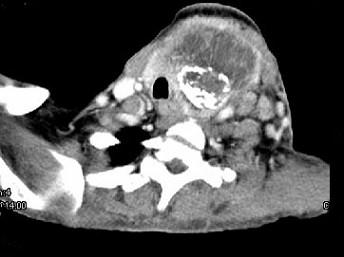

问题 女,64岁,发现双甲状腺肿大一月余,CT如图所示,最可能诊断为 ( )

选项 A、甲状腺转移癌 B、甲状腺结核 C、甲状腺腺瘤 D、甲状腺癌并淋巴结转移 E、结节性甲状腺肿

答案 D